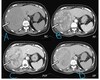

What pathology is seen here? Label A-D

Hepatocellular Carcinoma (HPC) -Multiphase study A: Non contrast: Mass is hypodense B: Arterial phase: Aorta bright, tumour enhanced, non uniform enhancement (mish mash) C: Portal venous phase D: Delayed phase